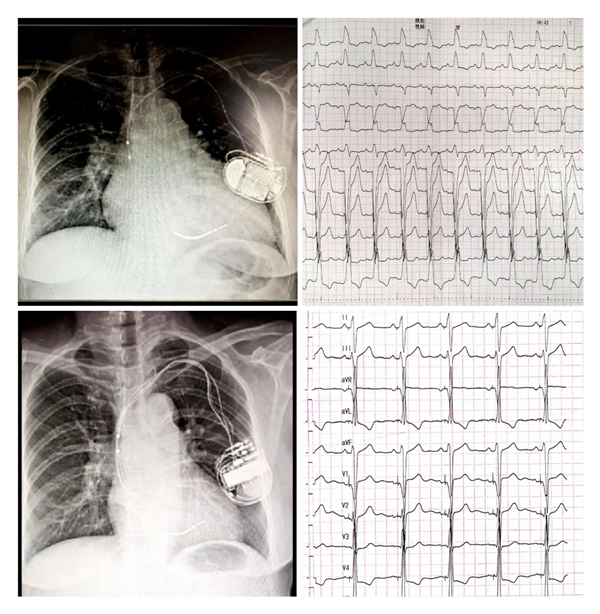

吃瓜网 为国内较早开展左束支起搏(LBBP)的中心之一,自2018年1月开展福建省首例LBBP以来,至今累计例数已近200例。中心采用黄伟剑教授的标准术式,手术成功率高、并发症少,随访导线参数稳定。此前起搏团队为1例外院CRT失败转诊我院的患者实行左束支起搏治疗得到了良好的疗效,LVD从80mm 缩小至52mm,LVEF 从24%升高至60%,心脏完全恢复正常。目前厦心常规开展这一技术以造服更多的心衰患者。

(上图左上为CRTD术前,外院植入ICD2年,右上是自身完左心电图;左下为CRTD术后一年,右下为CRTD术后心电图)